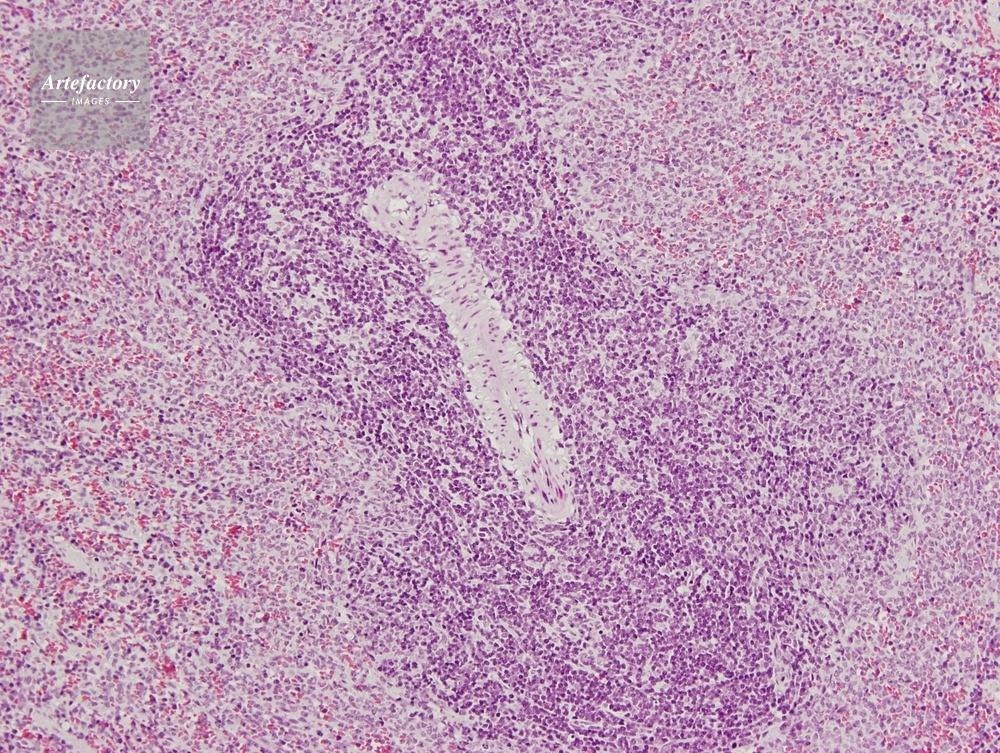

| 作品タイトル | マウス,脾臓 | モデルリリース | なし | |

| 作家 | OLYMPUS CORPORATION Technolab | プロパティリリース | なし | |